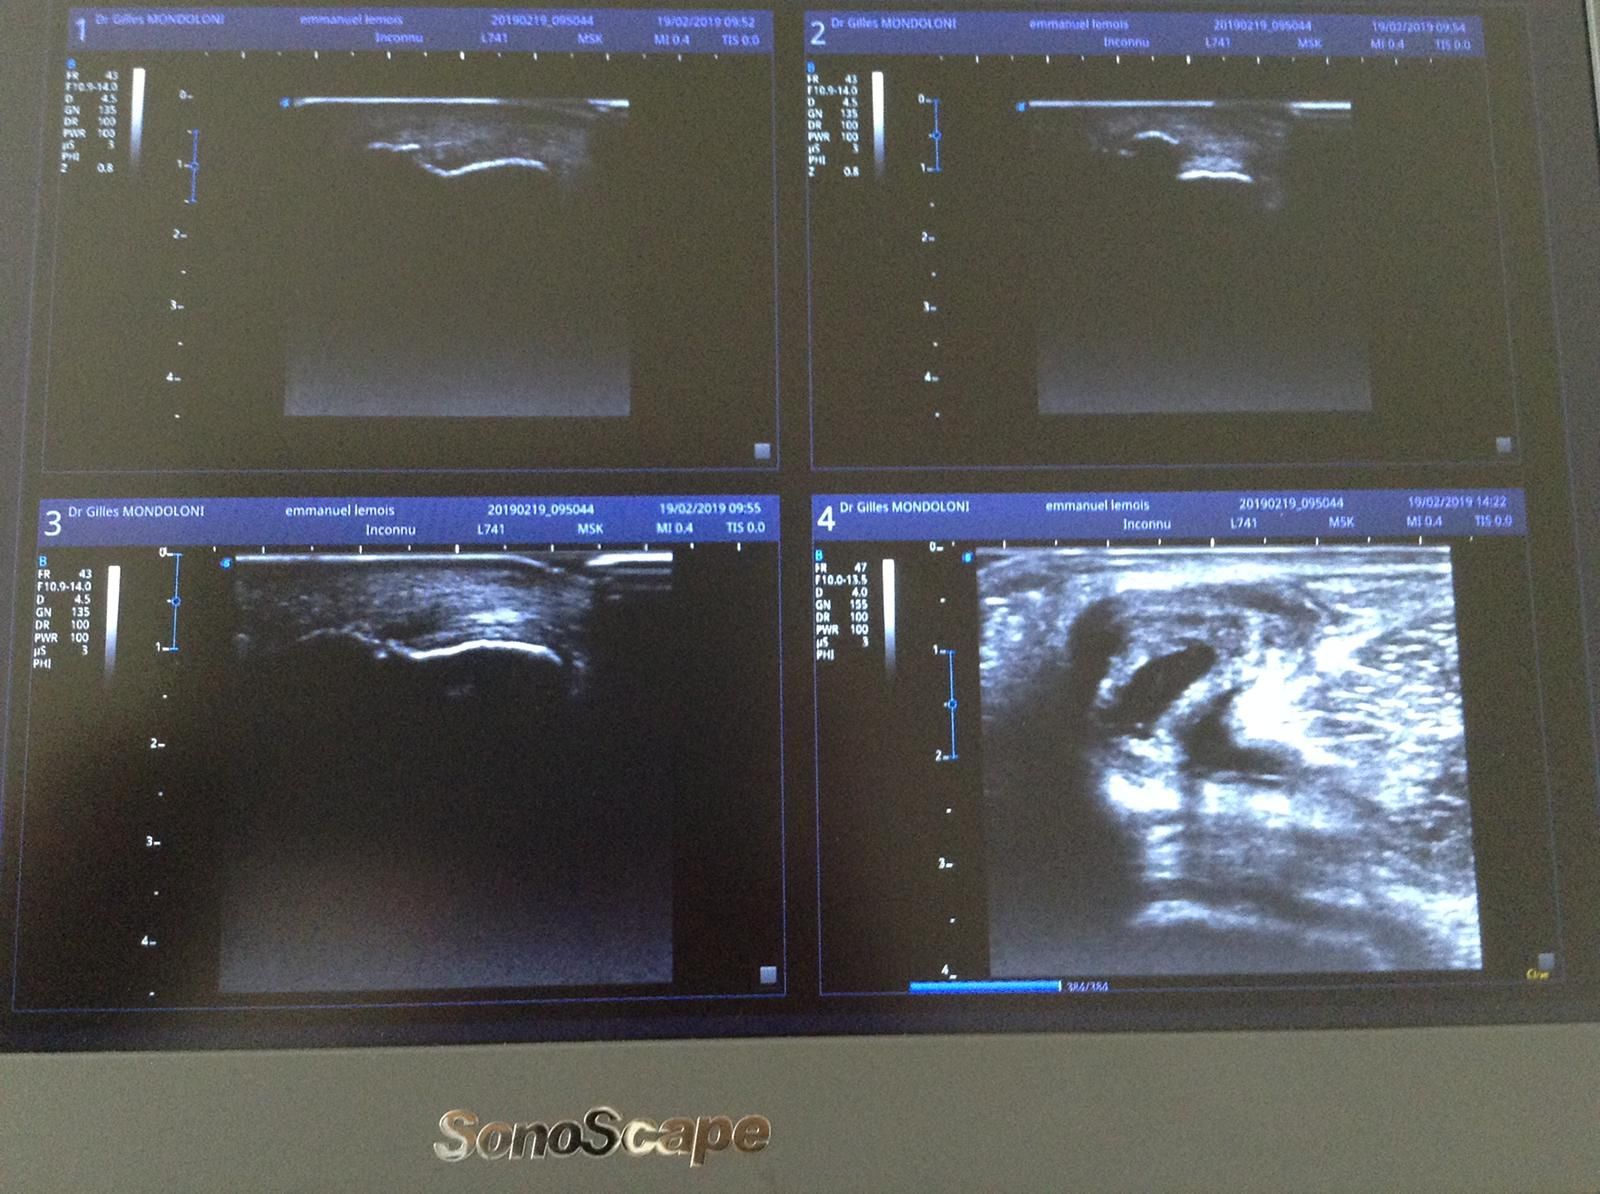

Le Docteur Gilles Mondoloni, médecin du sport à Châtillon, réalise des échographies musculosquelettiques.

L'échographie musculosquelettique est une technique d'imagerie médicale qui utilise des ondes sonores de haute fréquence pour visualiser les structures musculosquelettiques du corps, notamment les muscles, les tendons, les ligaments, les articulations et les tissus mous. Contrairement à d'autres modalités d'imagerie, comme la radiographie ou l'IRM, qui utilisent des rayonnements ionisants ou des champs magnétiques, l'échographie repose sur l'émission et la réception d'ondes sonores.

Cette méthode offre plusieurs avantages, notamment la capacité de réaliser des examens en temps réel, d'obtenir des images dynamiques des mouvements des structures anatomiques, et de guider précisément des procédures médicales telles que les injections ou les prélèvements de tissus. L'échographie musculosquelettique est fréquemment utilisée pour évaluer les troubles musculosquelettiques, les lésions tendineuses, les anomalies articulaires, les inflammations, et pour guider les traitements orthopédiques et rhumatologiques.

Grâce à sa capacité à fournir des images détaillées en temps réel, l'échographie musculosquelettique est un outil précieux dans le diagnostic et le suivi des affections liées aux tissus mous et aux articulations, offrant ainsi une approche non invasive et dynamique pour évaluer la santé musculosquelettique.